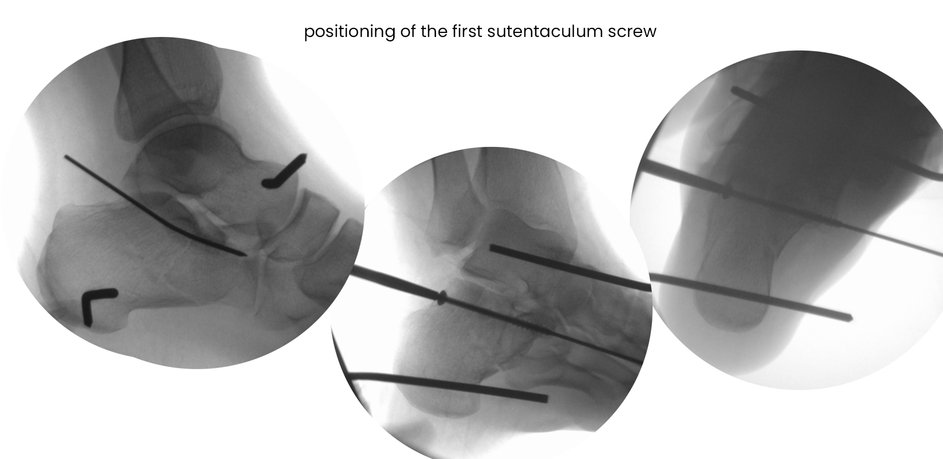

case 18ZJ, 23 years old, female, fall from horse, "atypical fracture" surgery after 2 days